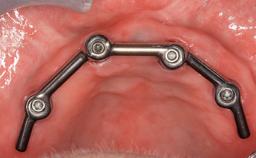

Maxillary Implant-supported Full-arch Removable Dental Prostheses for a Geriatric Patient: Sequencing the Treatment for an Optimal Outcome

A 90-year-old, essentially healthy woman requested assistance following what she determined was the loss of a dental restoration from a maxillary anterior tooth. She also complained of pain associated with tooth 11. The patient was assessed as relatively fit and healthy. She took medications for mild hypertension and to prevent angina attacks (atenolol and diltiazem). She had a form of arthritic joint degeneration affecting several joints; especially in her hands and fingers. When required she used an NSAID (meloxicam) for pain management. She reported living alone in a care facility that allows for independent living, with domestic support when and if necessary and primary medical triage when required.